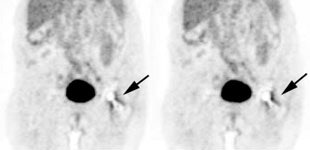

Bladder cancer: Dilute urinary activity in this patient's bladder allowed accurate detection of their bladder cancer (white arrows on CT, black arrows on PET scan). In general, urinary excretion of FDG limits evaluation of urinary tract malignancies, however, hydration and diuresis can improve diagnostic accuracy. |